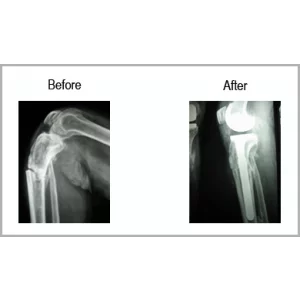

A male aged 65 years primarily treated in Kenya for fracture of tibia right, also had osteoarthritis of both knee. He was not able to put any weight over right leg.

His fracture and arthritis were treated with knee replacement with fracture fixation in a single surgery. Today his legs are normal and he can swim, walk and perform all his activities without any assistance.